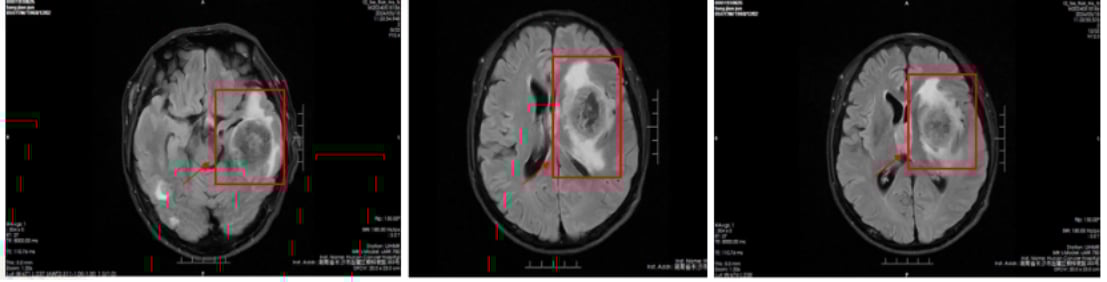

脑部转移灶变化:

治疗前(2024-5-14),头部影像显示脑内多发结节肿块,考虑为转移瘤。经过治疗后(2024-7-17),脑内多发转移瘤较前明显缩小、数量减少,且活性降低,显示出卓越的颅内病灶控制效果。

图3:治疗前头部影像

图4:治疗后头部影像